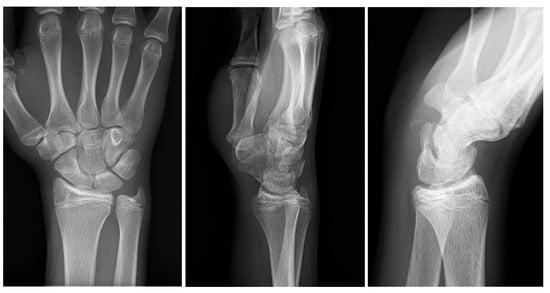

Initial conventional radiographic assessment showed no definitive fracture, with a potential suspicion of a proximal radius fracture (Figure 1). Due to significant tenderness over the radial fossa and pisiform, a CT scan was performed, confirming a nondisplaced scaphoid fracture and a suspected pisiform fracture with dislocation (Figure 2).

Figure 2.

Initial CT study with sagittal (A) and axial (B) images showing a non-displaced fracture of the pisiform bone (white arrows).